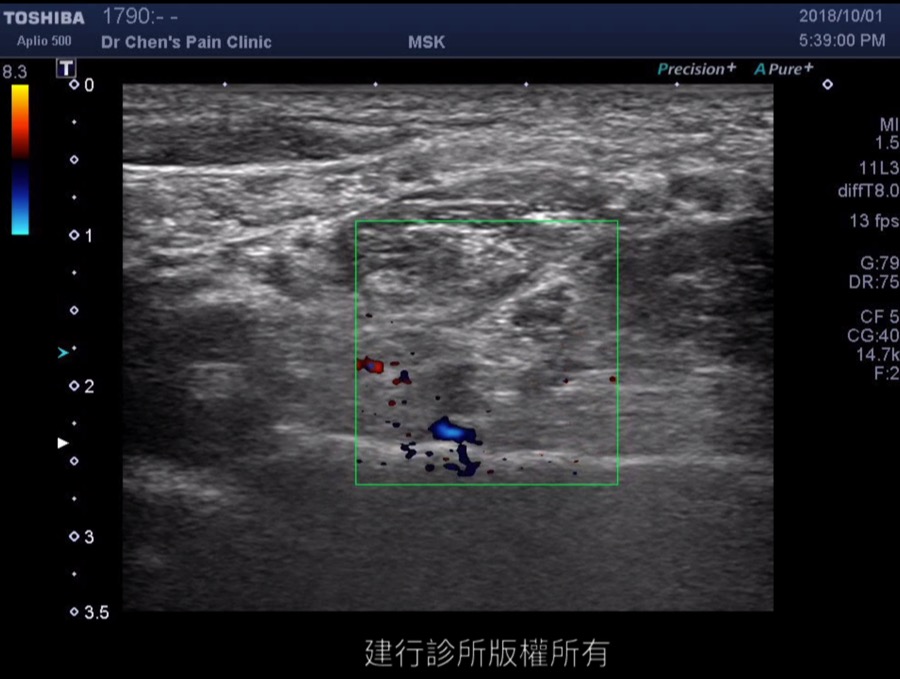

Radicular artery below C8 nerve root

當操作頸椎注射時,一定要看清楚這條動脈,避免危險